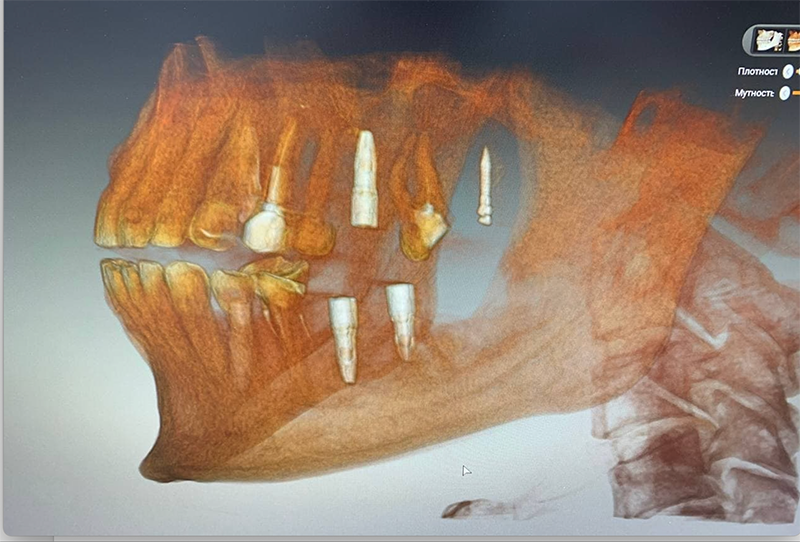

Вернёмся к нашей пациентке, у которой процесс удаления восьмёрки стал, к сожалению, более травматичным, чем предполагалось. Врач принимает решение и репонирует отломанный бугор, привинчивая его ортоимплантом. Покажу на снимке: на верхней челюсти, где раньше был восьмой зуб, виден такой контрастный гвоздь. Вот это и есть ортоимплант.

Здесь получилось удачно: ортоимплант врач будет использовать не только как исправление ошибки с отломанным бугром, но и по прямому назначению — с его помощью зуб можно переместить или изменить его наклон. Если вдруг запутались, то напомню — седьмой у нас съехал почти полностью на место шестого, нужно его передвинуть на своё законное место, чтобы можно было ставить коронку шестого.

Что имеем на этом этапе? У пациентки удалена верхняя восьмёрка, установлен ортоимплант, который будет тянуть семёрку на своё родное место. Установлена резиновая тяга. Удалена нижняя семёрка и нижняя восьмёрка, установлены импланты на правой стороне.